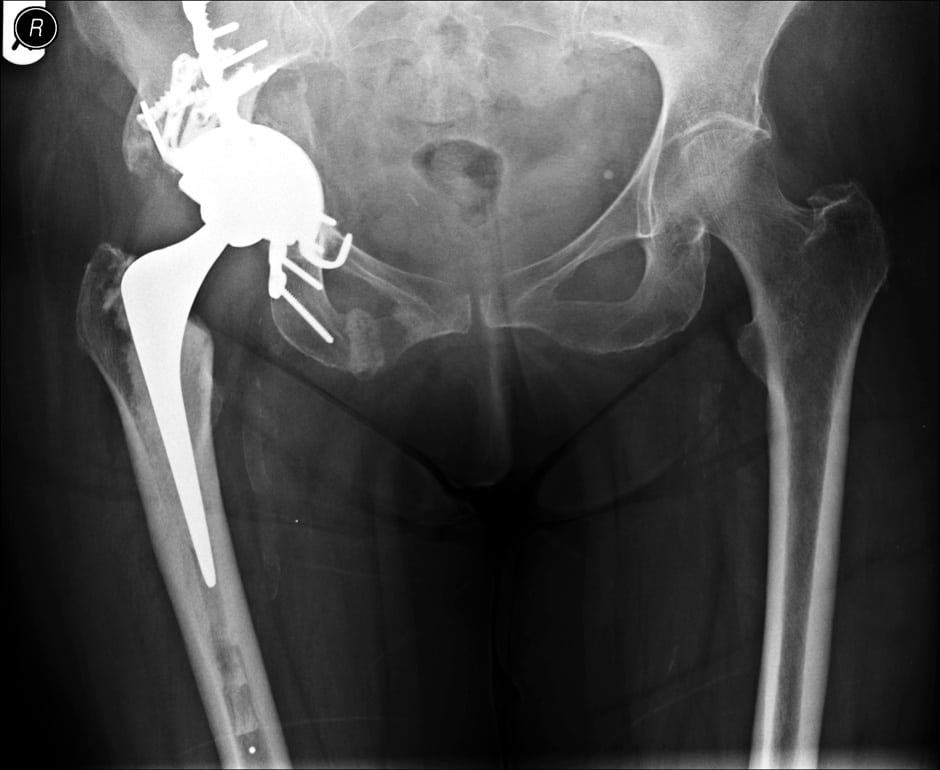

Revision Total Hip Replacement OrthoInfo AAOS

Revision Total Hip Replacement Dr Sunil Reddy Hip Revision Surgery Cost Uk advanced hip replacement and revision surgery. 1 this will help to reduce. Prices start at around £10,000 but other providers can charge as high as £15,000 depending on the area of the uk you live in. Prices also vary by provider and what’s included. hip replacement surgery is a procedure to replace your hip joint with artificial parts. Hip Revision Surgery Cost Uk.

What you need to know about revision hip replacements Dr Stuart MacKenzie Hip Revision Surgery Cost Uk the unit performs a large number of revision hip replacements each year for patients from across the uk and is recognised for its. Prices start at around £10,000 but other providers can charge as high as £15,000 depending on the area of the uk you live in. They generally cost more than the initial hip. Prices also vary by. Hip Revision Surgery Cost Uk.